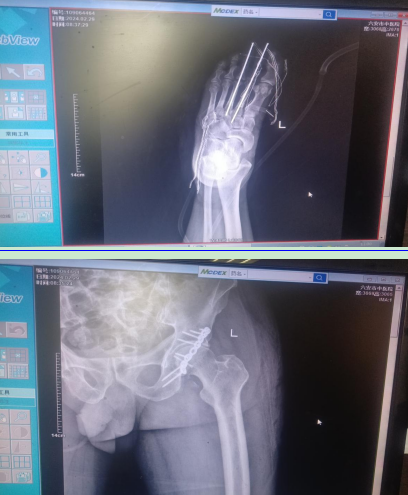

76岁的胡大爷深夜遭遇车祸,随后迅速被转送至我院ICU。胡大爷的伤势严重,左髋部骨盆骨折并伴有髋关节脱位,左足和左小腿均为开放伤,双侧肋骨也有多发性骨折。考虑到胡大爷当时的身体状况,不适合立即进行手术室的急诊手术。

我院骨伤二科的医生果断采取措施,在床边为胡大爷进行了左足和左小腿的清创术以及髋关节手法复位术,同时实施了左下肢骨牵引术,待胡大爷的身体状况逐渐好转后,又为其进行了髋臼骨折切开复位内固定术、足清创以及切开复位内固定术,成功帮助胡大爷稳定了病情,开启了康复之路。

多发伤患者术前图片

多发伤患者术后复查图片